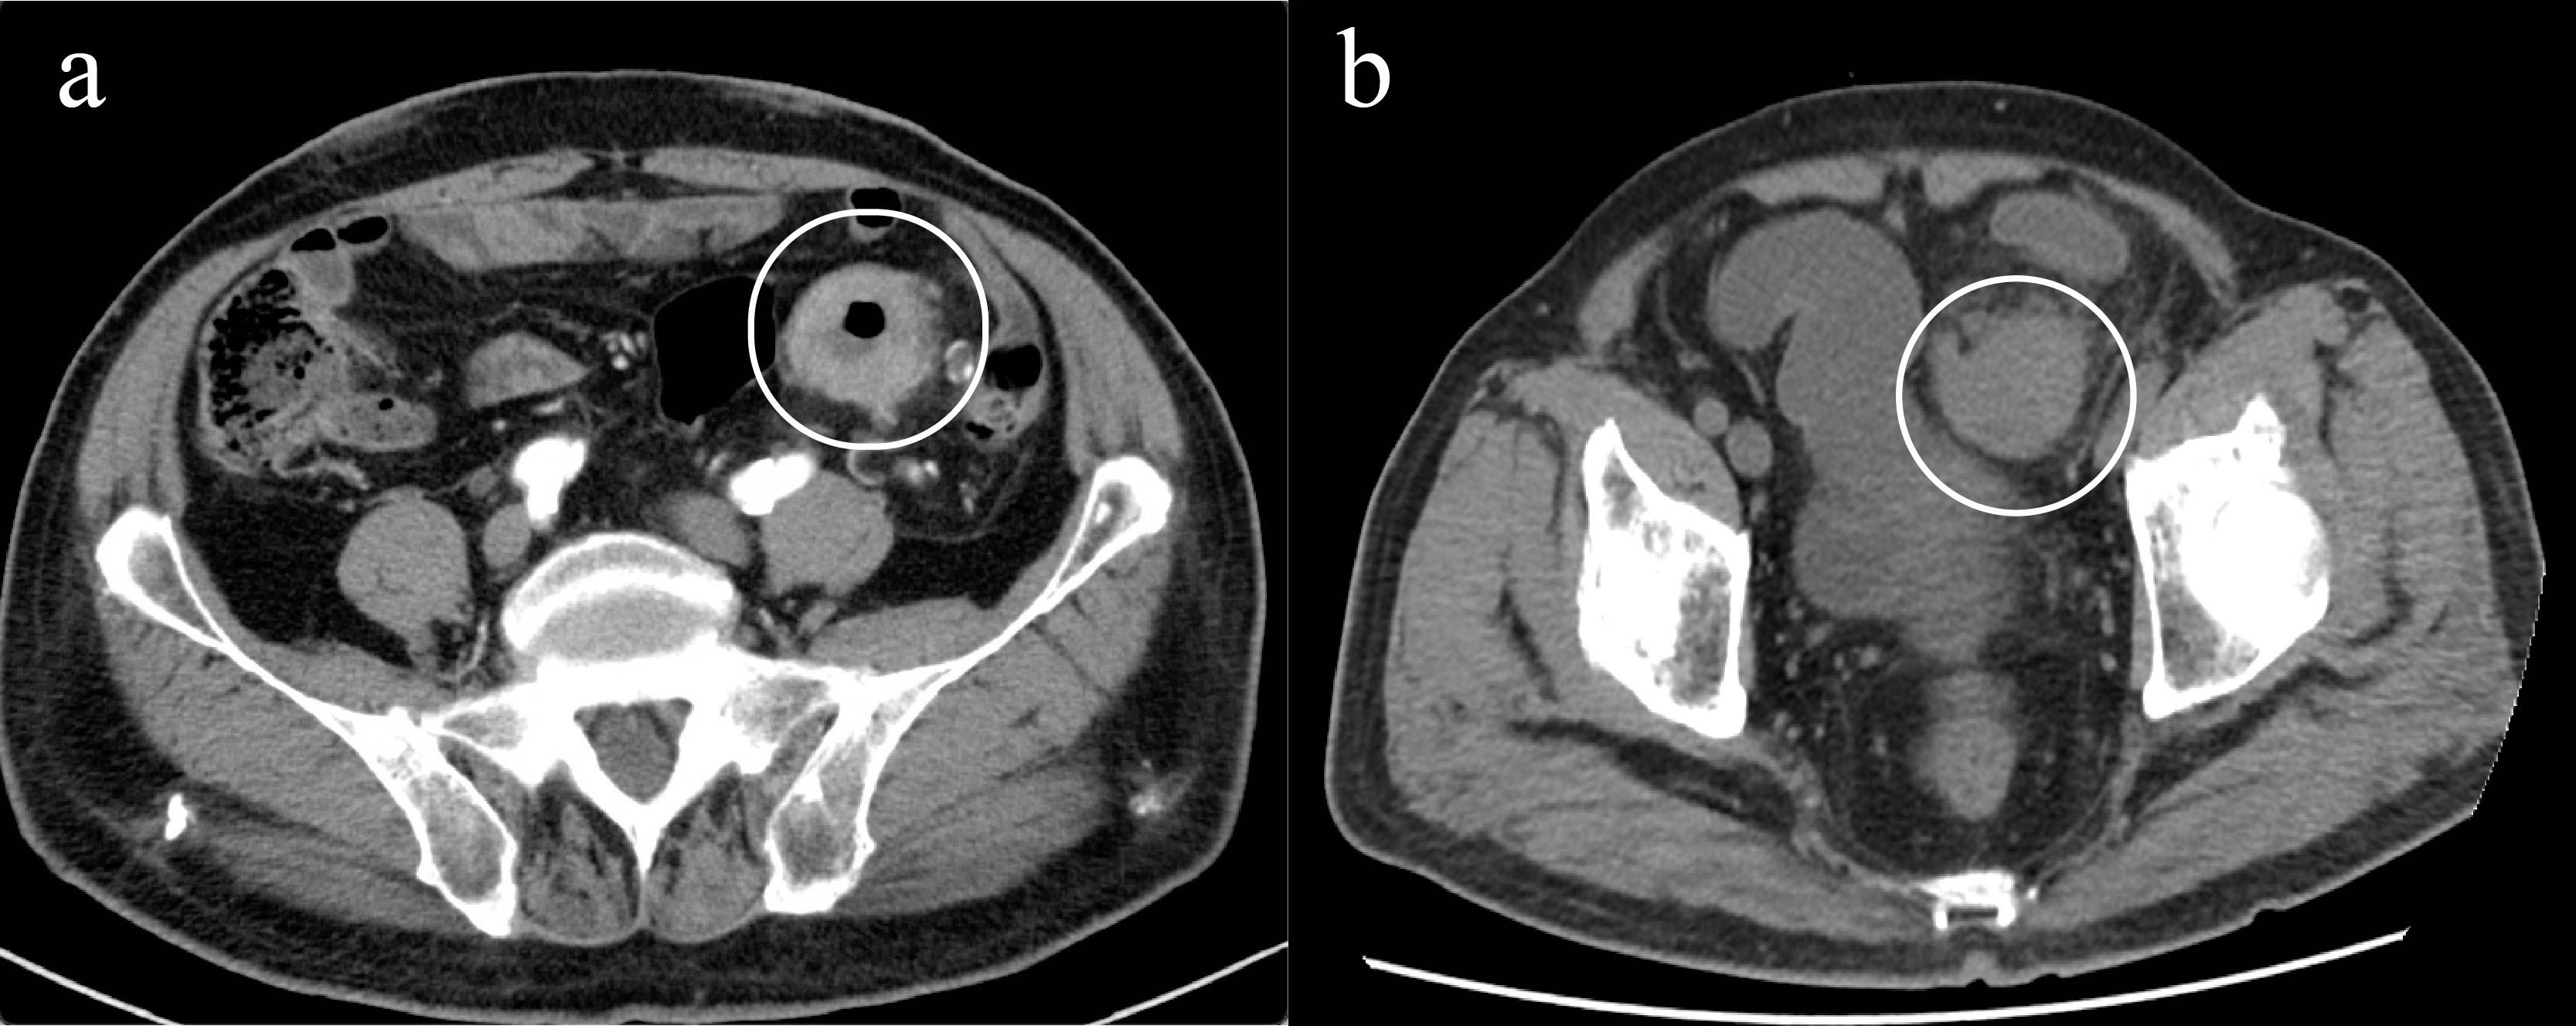

Gastric and colorectal cancers present significant therapeutic challenges, particularly in the elderly population, who often have comorbidities and diminished tolerance to standard treatments. This report describes an 85-year-old male with concurrent stage III gastric adenocarcinoma and stage IIIb microsatellite stable colorectal cancer, who declined both surgery and chemotherapy. Subsequently, the patient was treated with an innovative regimen consisting of endoscopic intratumoral injections of Oncolytic adenovirus H101 in combination with the PD-1 inhibitor tislelizumab. Following this combined therapeutic approach, the patient demonstrated notable tumor shrinkage and downstaging, accompanied by a reduction in serum tumor markers, including CEA and CA19-9. Additionally, there was an observed increase in CD8⁺ and CD4⁺ T-cell counts, indicating systemic immune activation. The treatment was well-tolerated, with the only reported adverse event being mild fever. The patient achieved nearly 4 months of progression-free survival and a substantial improvement in quality of life. This case highlights the potential of combining oncolytic virotherapy with PD-1 inhibition as a promising and novel personalized strategy for treating elderly patients with advanced gastrointestinal cancers who are unsuitable candidates for conventional therapies.